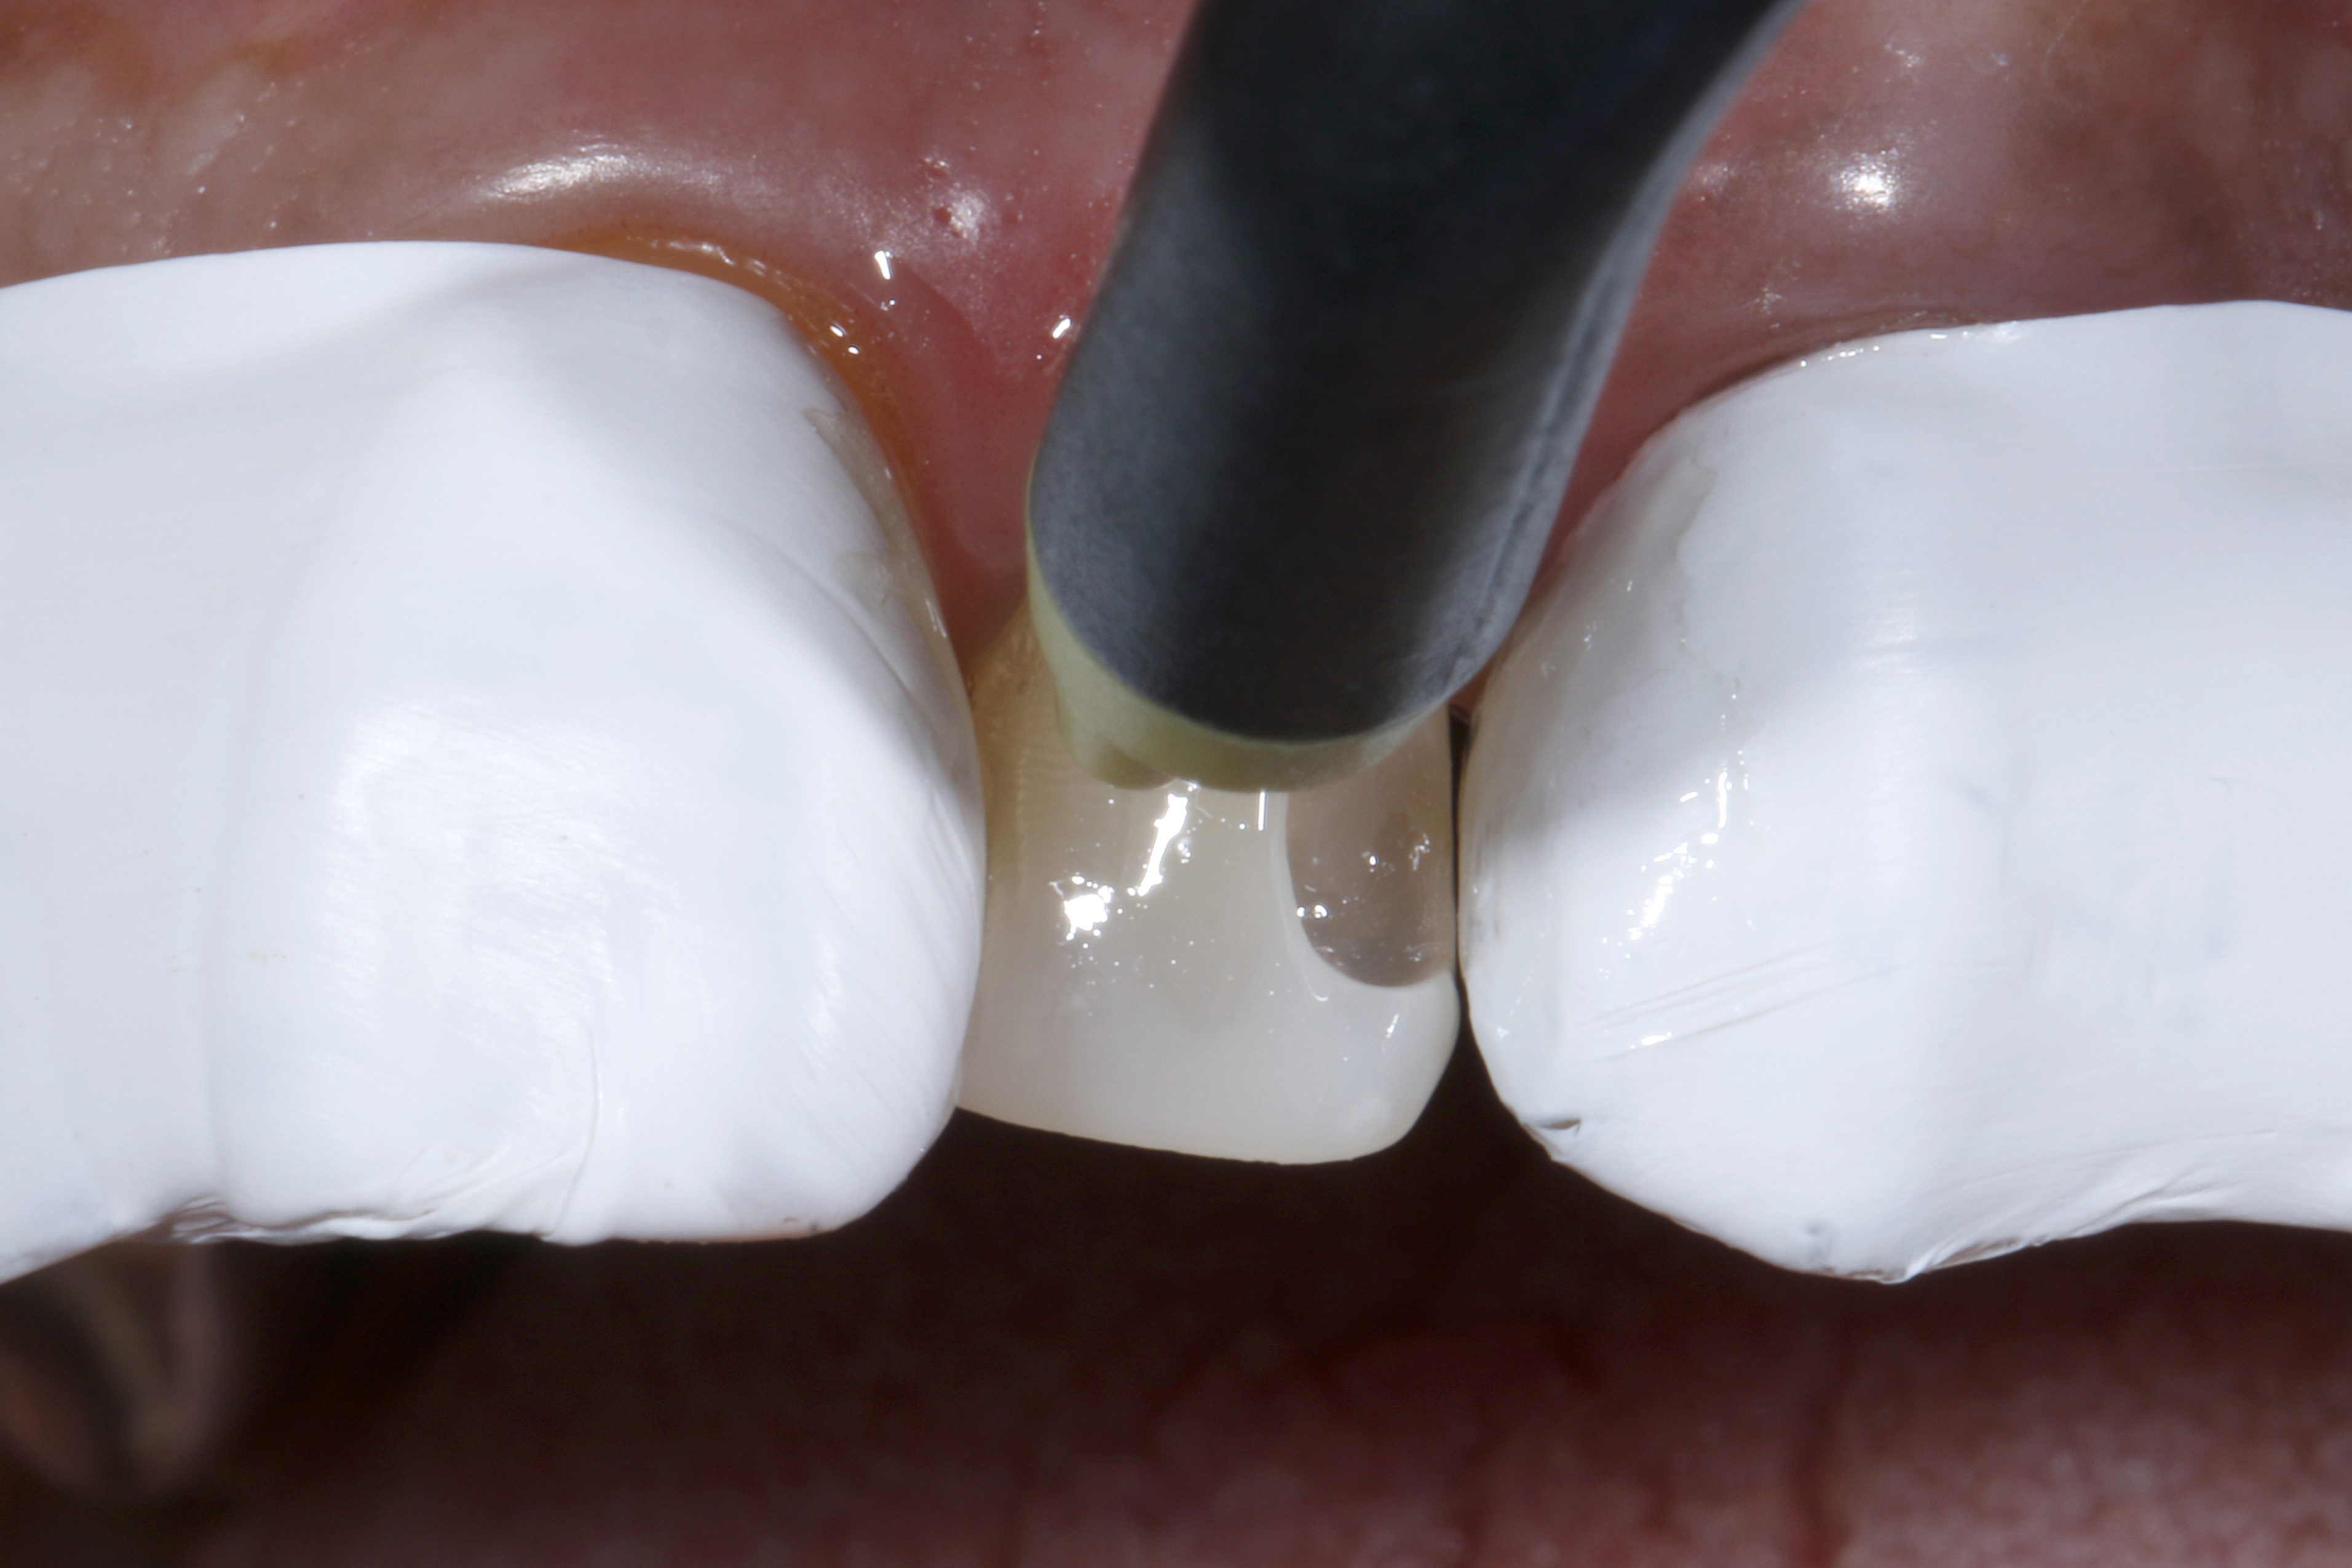

Ryc. 5. Odsunięcie dziąsła brzeżnego za pomocą nici retrakcyjnej w celu odsłonięcia brzegu preparacji od strony przyszyjkowej, co spowodowało krwawienie z bruzdy

Ryc. 6. Do bruzdy dziąsłowej od strony wargowej nałożono pastę retrakcyjną (Retraction Paste, VOCO GmbH, Cuxhaven) o działaniu ściągającym.

Ryc. 7. Po 2 minutach ekspozycji pastę ostrożnie usunięto za pomocą sprayu wodno-powietrznego z użyciem podciśnienia.

Następnie obszar osuszono sprężonym powietrzem. Miejscowe krwawienie w okolicy dziąseł zatamowano łatwo i skutecznie za pomocą pasty retrakcyjnej zawierającej chlorek glinu i kaolin (ryc. 8). Tylko czyste i suche pole zabiegowe pozwala na dalszą pracę bez zanieczyszczeń. W kolejnym etapie zabezpieczono oba sąsiednie zęby taśmą teflonową (ryc. 9).